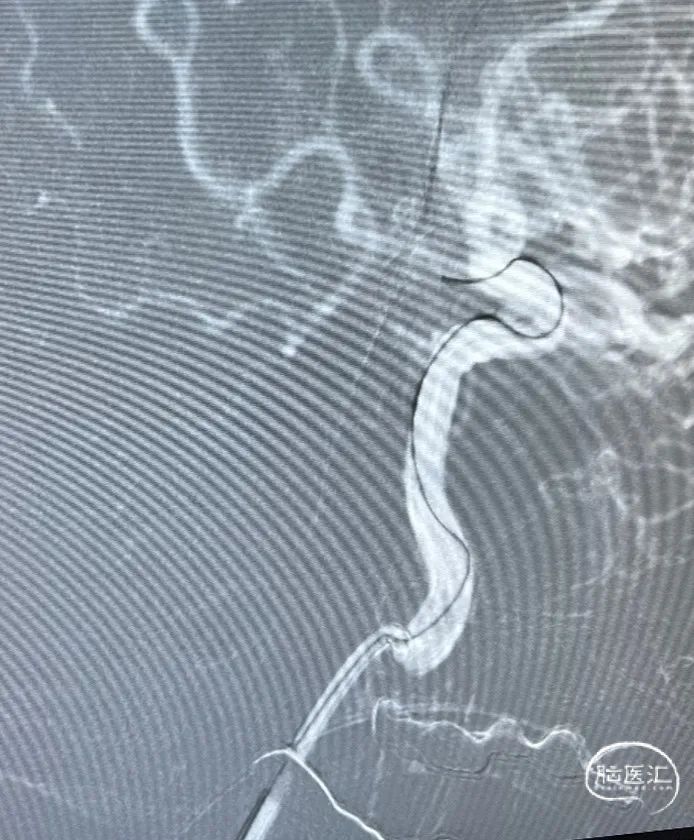

左侧颈内动脉迂曲,在SL-10微导管及Synchro微导丝配合下将6F Envoy输送至左侧岩骨段近端。

XT-17支架微导管和SL-10栓塞导管到位(如下视频)。

预填部分2mm*4cm Target弹簧圈进行成篮,然后将4.5*21mm Atlas支架到位并进行半释放,半释放支架后,继续填入2mm*4cm Target弹簧圈。

将Atlas支架全部释放(如左动态影像)

Target 2mm*4cm弹簧圈成篮满意,支架打开良好。